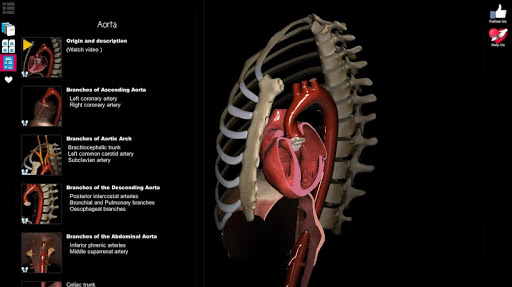

A true and totally 3D app for studying human anatomy, built on an advanced interactive 3D touch interface.

★ Circulation (arteries, vein and heart)